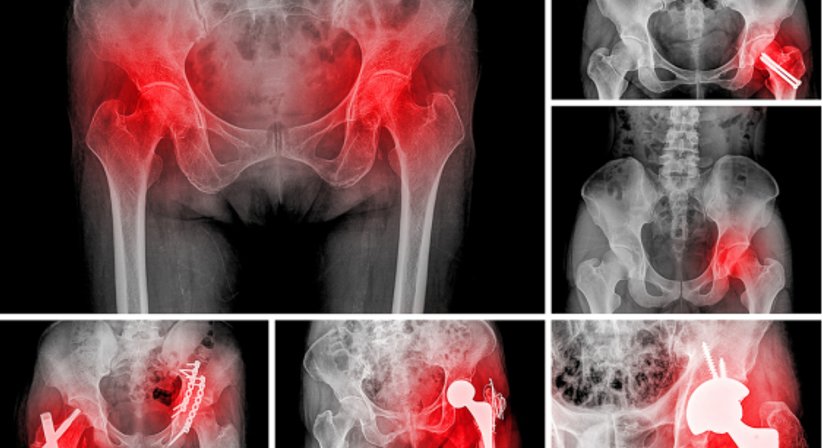

Hüftprothese

Für die Implantation einer Hüftprothese stehen unterschiedliche Prothesen als auch Operationsmethoden zu Wahl. Welches künstliche Hüftgelenk zum Einsatz kommt orientiert sich, ebenso wie die Wahl der Operationsmethode, an zahlreichen individuellen Faktoren und wird vorab ausführlich besprochen.